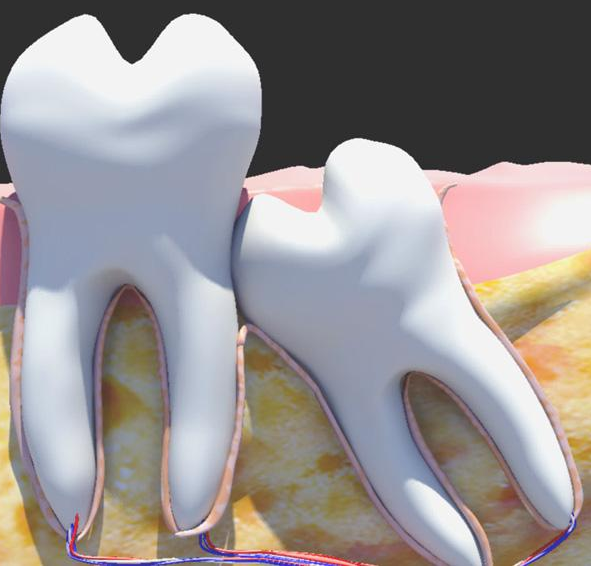

这项技术叫牙移植,自体牙移植术是除常规固定义齿、活动义齿以及种植义齿修复缺失牙以外的另一种修复缺牙的方法。但其实早在古埃及时代,奴隶们就被迫把自己的牙齿移植给奴隶主了。

想想这种是忍受不了的,不仅不卫生,匹配度不高,不过现在的牙移植技术已经不断成熟,拥有了自体牙移植项目,牙齿也实现了自产自销!而且成功率都是高达80%。

不过也有很多人说了,如今有那么多种方法,可以种植牙,为何要选牙移植呢?大家都知道种植牙费用都在5千到1万之间,用自己的牙费用会省很多,而且你自己的牙齿,适应度,稳定性肯定会高,不容易引发牙周病。

通过牙医妙手的“乾坤大挪移”,智齿就成了我们补牙的理想替补。所以,今后大家千万不要,觉得智齿一无是处啦,可以充分利用将它“变废为宝”。